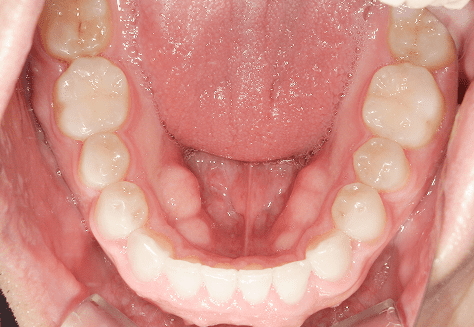

M.U

治療前

治療後

主訴

下の歯が特にガタガタなのが気になる。上の前歯が1本反対になっている。

診断

下顎前突・叢生・反対咬合

年齢/性別

20代/男性

抜歯部位

非抜歯

使用装置

上下インビザライン(PBM使用)

保定装置

ビベラリテーナー

料金

初回資料採得・・・・・・・30,000円

診断料・・・・・・・・・・33,000円

動的治療終了時資料採得・・5,500円 -

基本料金

950,000円

診察料金

5,500円×16回

治療期間

1年7カ月